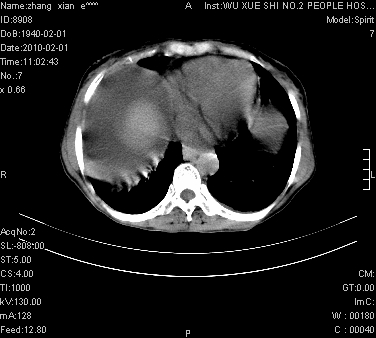

标题: CT24434:70岁 女 腹胀,腹水原因待查 [打印本页]

标题: CT24434:70岁 女 腹胀,腹水原因待查

大量腹水,脾囊肿可能性大,建议增强

考虑子宫癌并腹水 脾囊肿

大量腹水,右肾、脾囊肿可能性大          考虑左侧附件区占位,建议增强